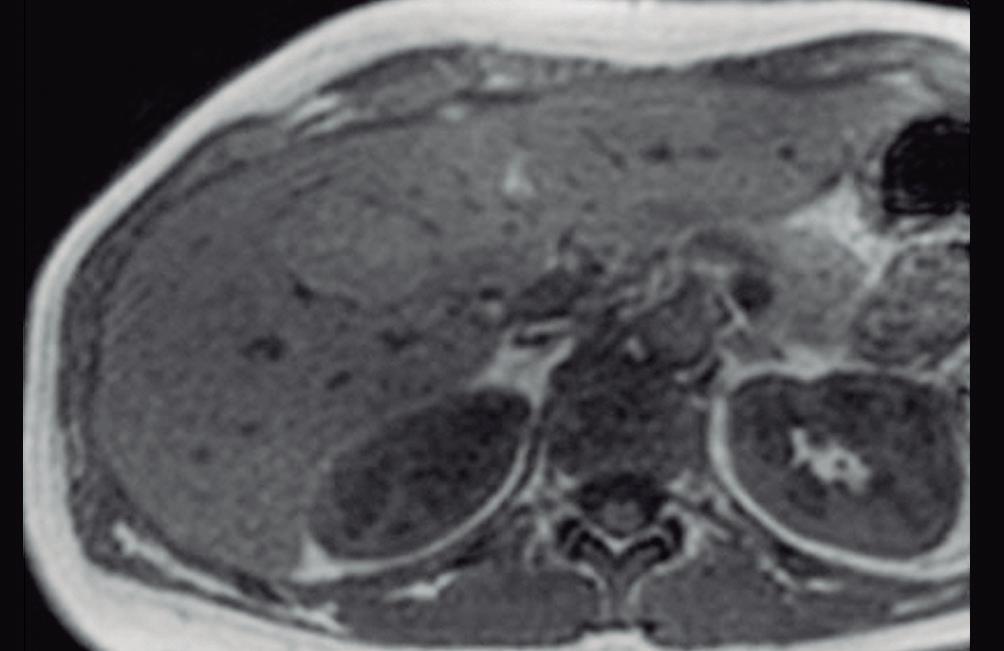

En la TC los hemangiomas son lesiones de bordes netos y frecuentemente de contornos lobulados. Al estar compuestas por vasos, su densidad es igual a la del pool sanguíneo, tanto en las imágenes sin contraste como en las diferentes fases de la evaluación poscontraste. El refuerzo es típicamente globular y progresivo, de forma centrípeta.

(Figura 1) En los hemangiomas de mayor tamaño el pasaje del contraste al centro de la lesión toma más tiempo e incluso no ocurre en aquellos más voluminosos.

A, en fase arterial; B, y en fase de equilibrio; C, que muestran una lesión de contornos lobulados y bordes netos en el lóbulo hepático derecho que presenta refuerzo globular, progresivo e isodenso con las estructuras vasculares.

Lesiones benignas localizadas en el hígado desde la mirada de las imágenes Mariano Volpacchio Figura 1. Hemangioma en tomografía computada. Imágenes axiales de la TC sin contraste Figura 2. Hemangioma en la RM. Imágenes axiales de la RM en secuencia T2 con supresión grasa con el refuerzo similar a las estructuras vasculares de aspecto globular y progresivo en sucesivas fases. Nótese la heterogeneidad del hemangioma de mayor tamaño en segmento VI. A B C